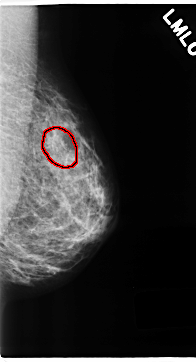

C_0199_1.LEFT_CC

FILE: C_0199_1.LEFT_CC.OVERLAY

TOTAL_ABNORMALITIES 1

ABNORMALITY 1

LESION_TYPE CALCIFICATION TYPE PLEOMORPHIC DISTRIBUTION CLUSTERED

ASSESSMENT 5

SUBTLETY 4

PATHOLOGY MALIGNANT

TOTAL_OUTLINES 1

BOUNDARY